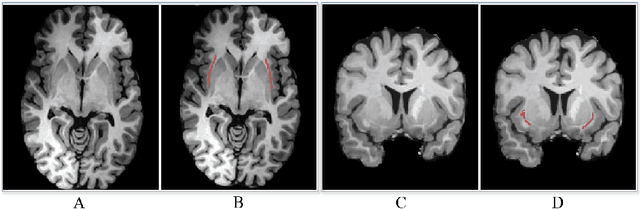

Abstract:Segmentationand parcellation of the brain has been widely performed on brain MRI using atlas-based methods. However, segmentation of the claustrum, a thin and sheet-like structure between insular cortex and putamen has not been amenable to automatized segmentation, thus limiting its investigation in larger imaging cohorts. Recently, deep-learning based approaches have been introduced for automated segmentation of brain structures, yielding great potential to overcome preexisting limitations. In the following, we present a multi-view deep-learning based approach to segment the claustrum in T1-weighted MRI scans. We trained and evaluated the proposed method on 181 manual bilateral claustrum annotations by an expert neuroradiologist serving as reference standard. Cross-validation experiments yielded median volumetric similarity, robust Hausdor? distance and Dice score of 93.3%, 1.41mm and 71.8% respectively which represents equal or superior segmentation performance compared to human intra-rater reliability. Leave-one-scanner-out evaluation showed good transfer-ability of the algorithm to images from unseen scanners, however at slightly inferior performance. Furthermore, we found that AI-based claustrum segmentation benefits from multi-view information and requires sample sizes of around 75 MRI scans in the training set. In conclusion, the developed algorithm has large potential in independent study cohorts and to facilitate MRI-based research of the human claustrum through automated segmentation. The software and models of our method are made publicly available.